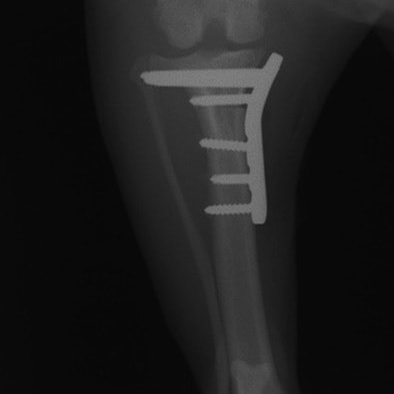

ミニチュアダックスフンド 9歳 未去勢♂

突然の非負重性の右後肢跛行を主訴に来院されました。触診上、右膝の伸展痛が認められ、整形外科学的検査において右膝の内外側の膝蓋骨脱臼(Grade Ⅱ)、脛骨圧迫テストで陽性が認められました。神経学的検査において特に異常は認められませんでした。レントゲン検査において、関節液の貯留所見や脛骨の前方変位の所見は認められませんでいた。

関節穿刺を行い、好中球はなく、少数のマクロファージや滑膜細胞が認められるました。膝蓋骨脱臼および前十字靭帯断裂による退行性の関節炎を疑い、関節鏡検査を実施いたしました。関節鏡検査では、重度の滑膜炎および前十字靭帯の完全断裂が認められました。内外側とも半月板に損傷は認められませんでした。

■ 外科的治療法

断裂前十字靭帯の除去を行いました。外側方向からのテンションが著しく、外側広筋と膝関節外側支帯の解放を行いました。膝関節伸展機構の著しいアライメント異常が認められたため、脛骨粗面転移術を実施しました。

写真の膝関節の垂直線を綿棒の木柄が表しており、遠位の脛骨粗面との位置関係が平行ではありません。

転移側の骨床は犬種特有の変形した表面であったため、転移後の骨片の圧着状態が改善するように変形表面をラウンドバーにて切削しました。滑車溝の著しい低形成が認められたため、滑車溝形成術を実施いたしました。

切断された関節包の縫縮を行いました。前十字靭帯断裂後の不安定性と内旋を解消するために、人工靭帯(fiber wire)によるラテラルスーチャー法を併用し安定化を図りました。

術後、整形外科学的検査における脛骨圧迫テストや前方引き出し兆候は認められませんでした。